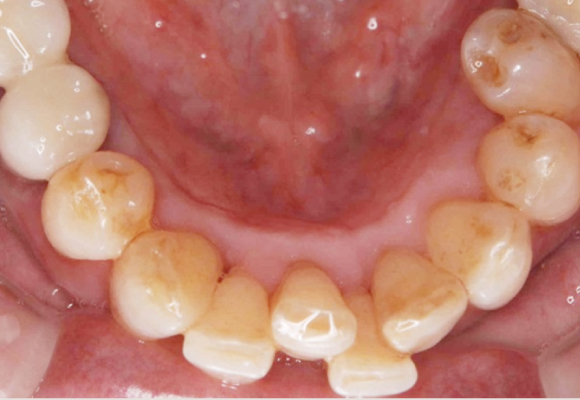

治療前(症例)

治療後(症例)

治療前(症例)

治療後(症例)